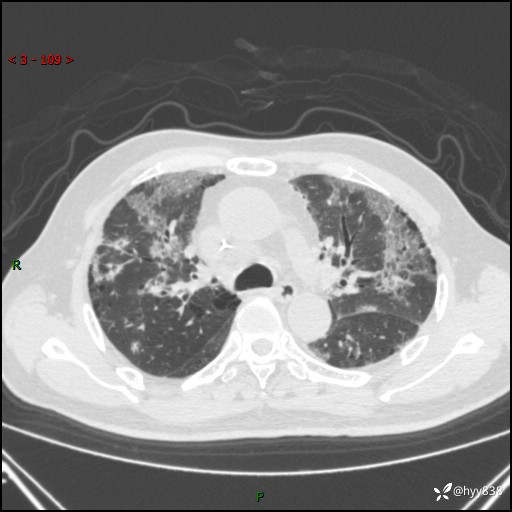

患者性别:男

患者年龄:64岁

简要病史:肝内胆管癌综合治疗后2周余,咳嗽、发热,咳白色泡沫痰。

辅助检查:CT

临床诊断:感染?

讨论:病变性质?